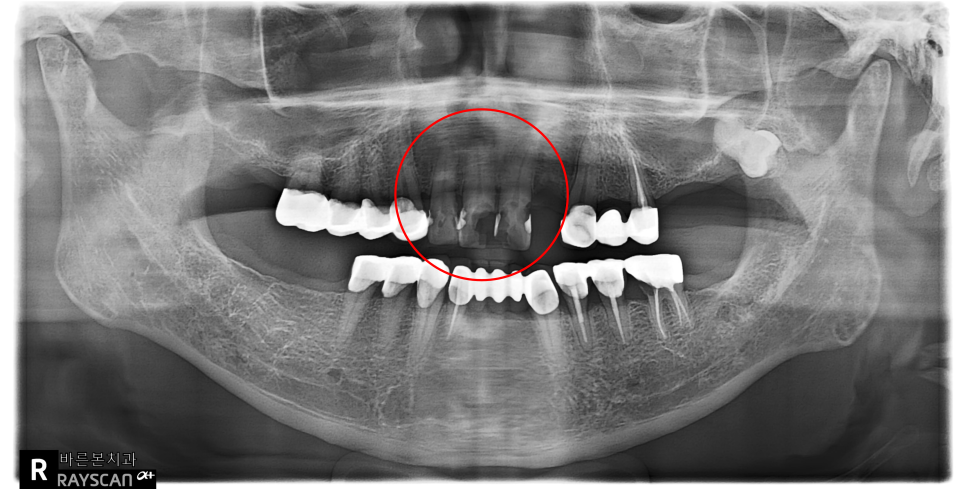

23.11.28(초진) – 56y 심OO님

” 앞니통증이 너무 심해요. 깨진지는 오래되었고

직장근처에서 임시 재료를 넣어줬어요 ” 라고

말씀하시며 수원치과추천로 내원하신 환자분의

x-ray 사진입니다.

빨강색동그라미 부분이 심한 앞니통증의

원인인 치아들입니다.

앞니깨짐도 관찰이되고 자세히 보면

뿌리끝 염증도 보이네요.